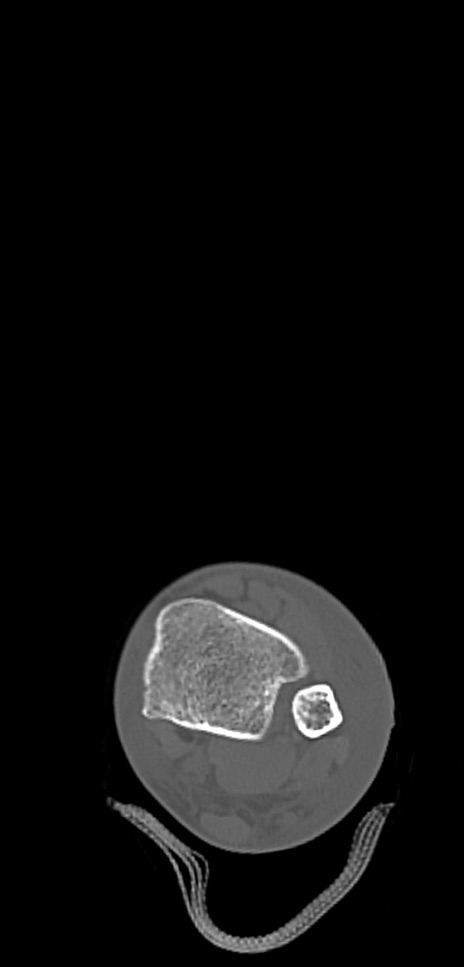

症例37 左足関節CT(横断像)

左足関節CT

3D再構成